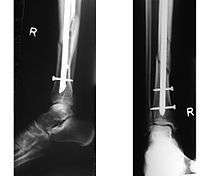

Osteosynthesis is the reduction and internal fixation of a bone fracture with implantable devices that are usually made of metal. It is a surgical procedure with an open or per cutaneous approach to the fractured bone. Osteosynthesis aims to bring the fractured bone ends together and immobilize the fracture site while healing takes place. In a fracture that is rigidly immobilized the fracture heals by the process of intramembranous ossification.